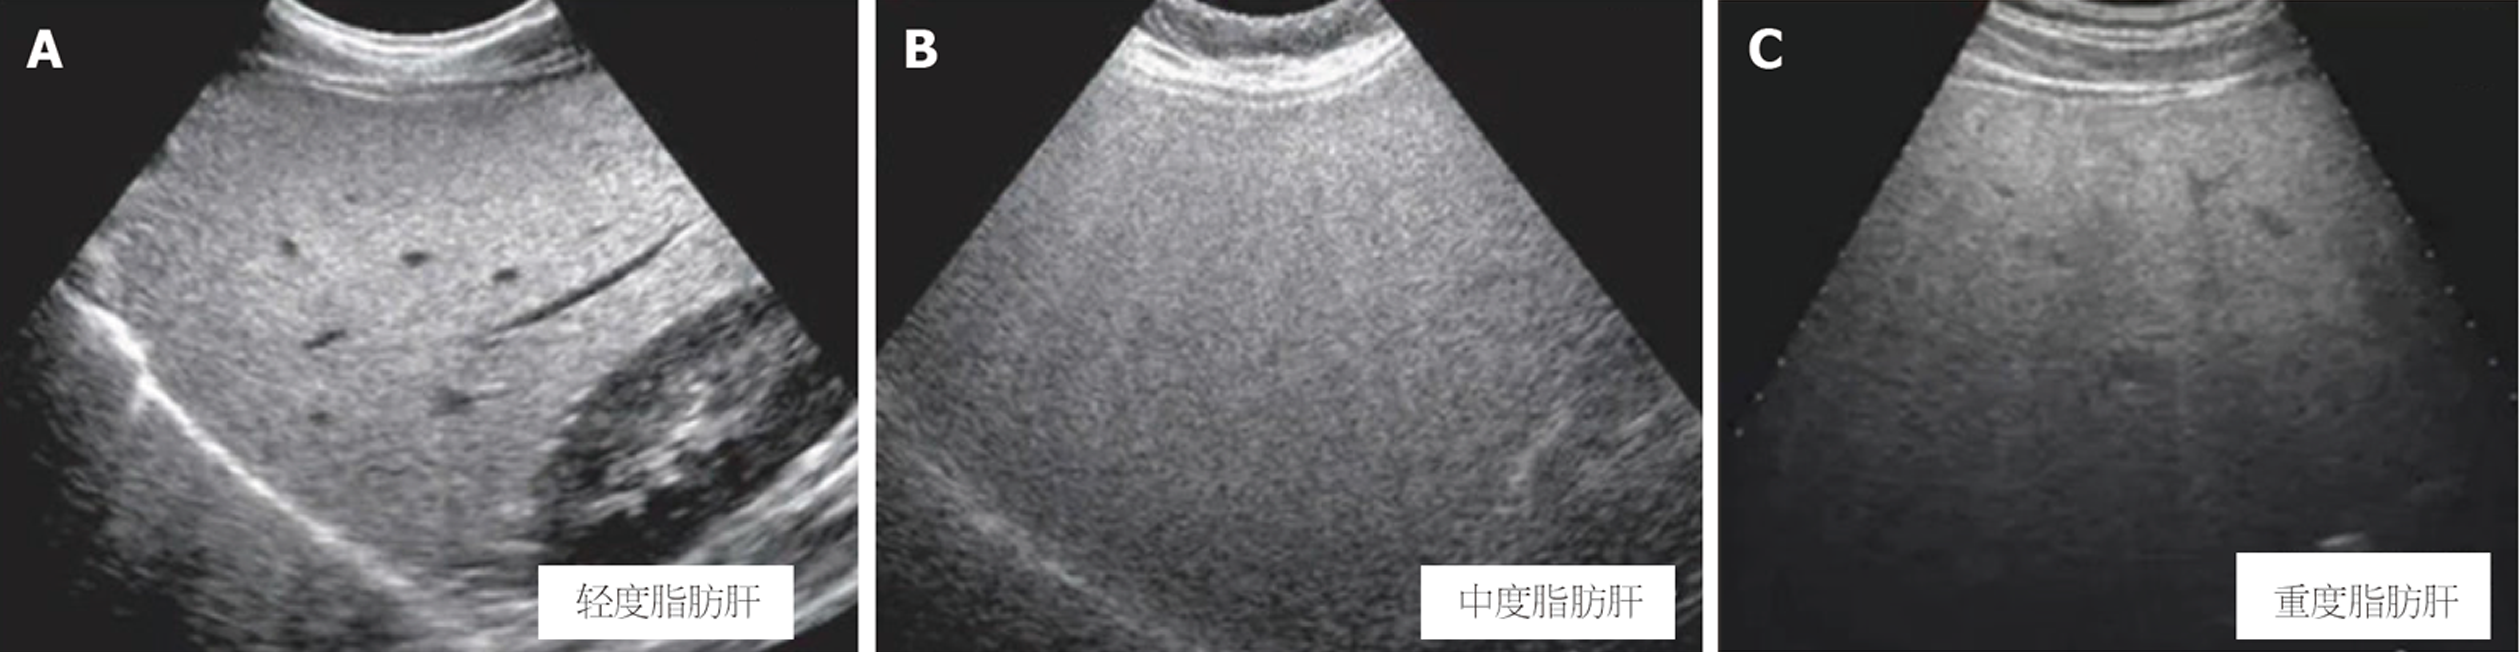

不同肝脂肪变程度患者之间比较, 轻度、中度、重度患者UDFF、MRI PDFF依次升高, 两两比较差异均有统计学意义(P<0.05). ICC分析显示, 轻度患者中: ICC = 0.723, 提示两者具有中等一致性; 中度与重度患者中, ICC均>0.850, 提示两者均具有优秀的一致性, 即UDFF在较高脂肪变时与MRI-MRI PDFF高度一致. Bland-Altman分析显示, 轻度患者中, Bias = 0.920%, 提示UDFF略高估, LOA范围较宽(-0.980至2.820), 提示低值区间一致性较低; 中度和重度患者中, Bias偏差缩小, 尤其是重度患者几乎无偏差(Bias = -0.25%), LOA变窄, 表明中高脂肪变时两种方法高度一致. 异方差性检验显示, 测量差值的绝对值与平均值间无显著相关性(r = 0.182, P = 0.092), 表明数据不存在显著的异方差性, 所报告的总体Bias与LOA在全测量范围内具有稳定性. 见表3. 不同肝脂肪变程度患者超声表现见图3.